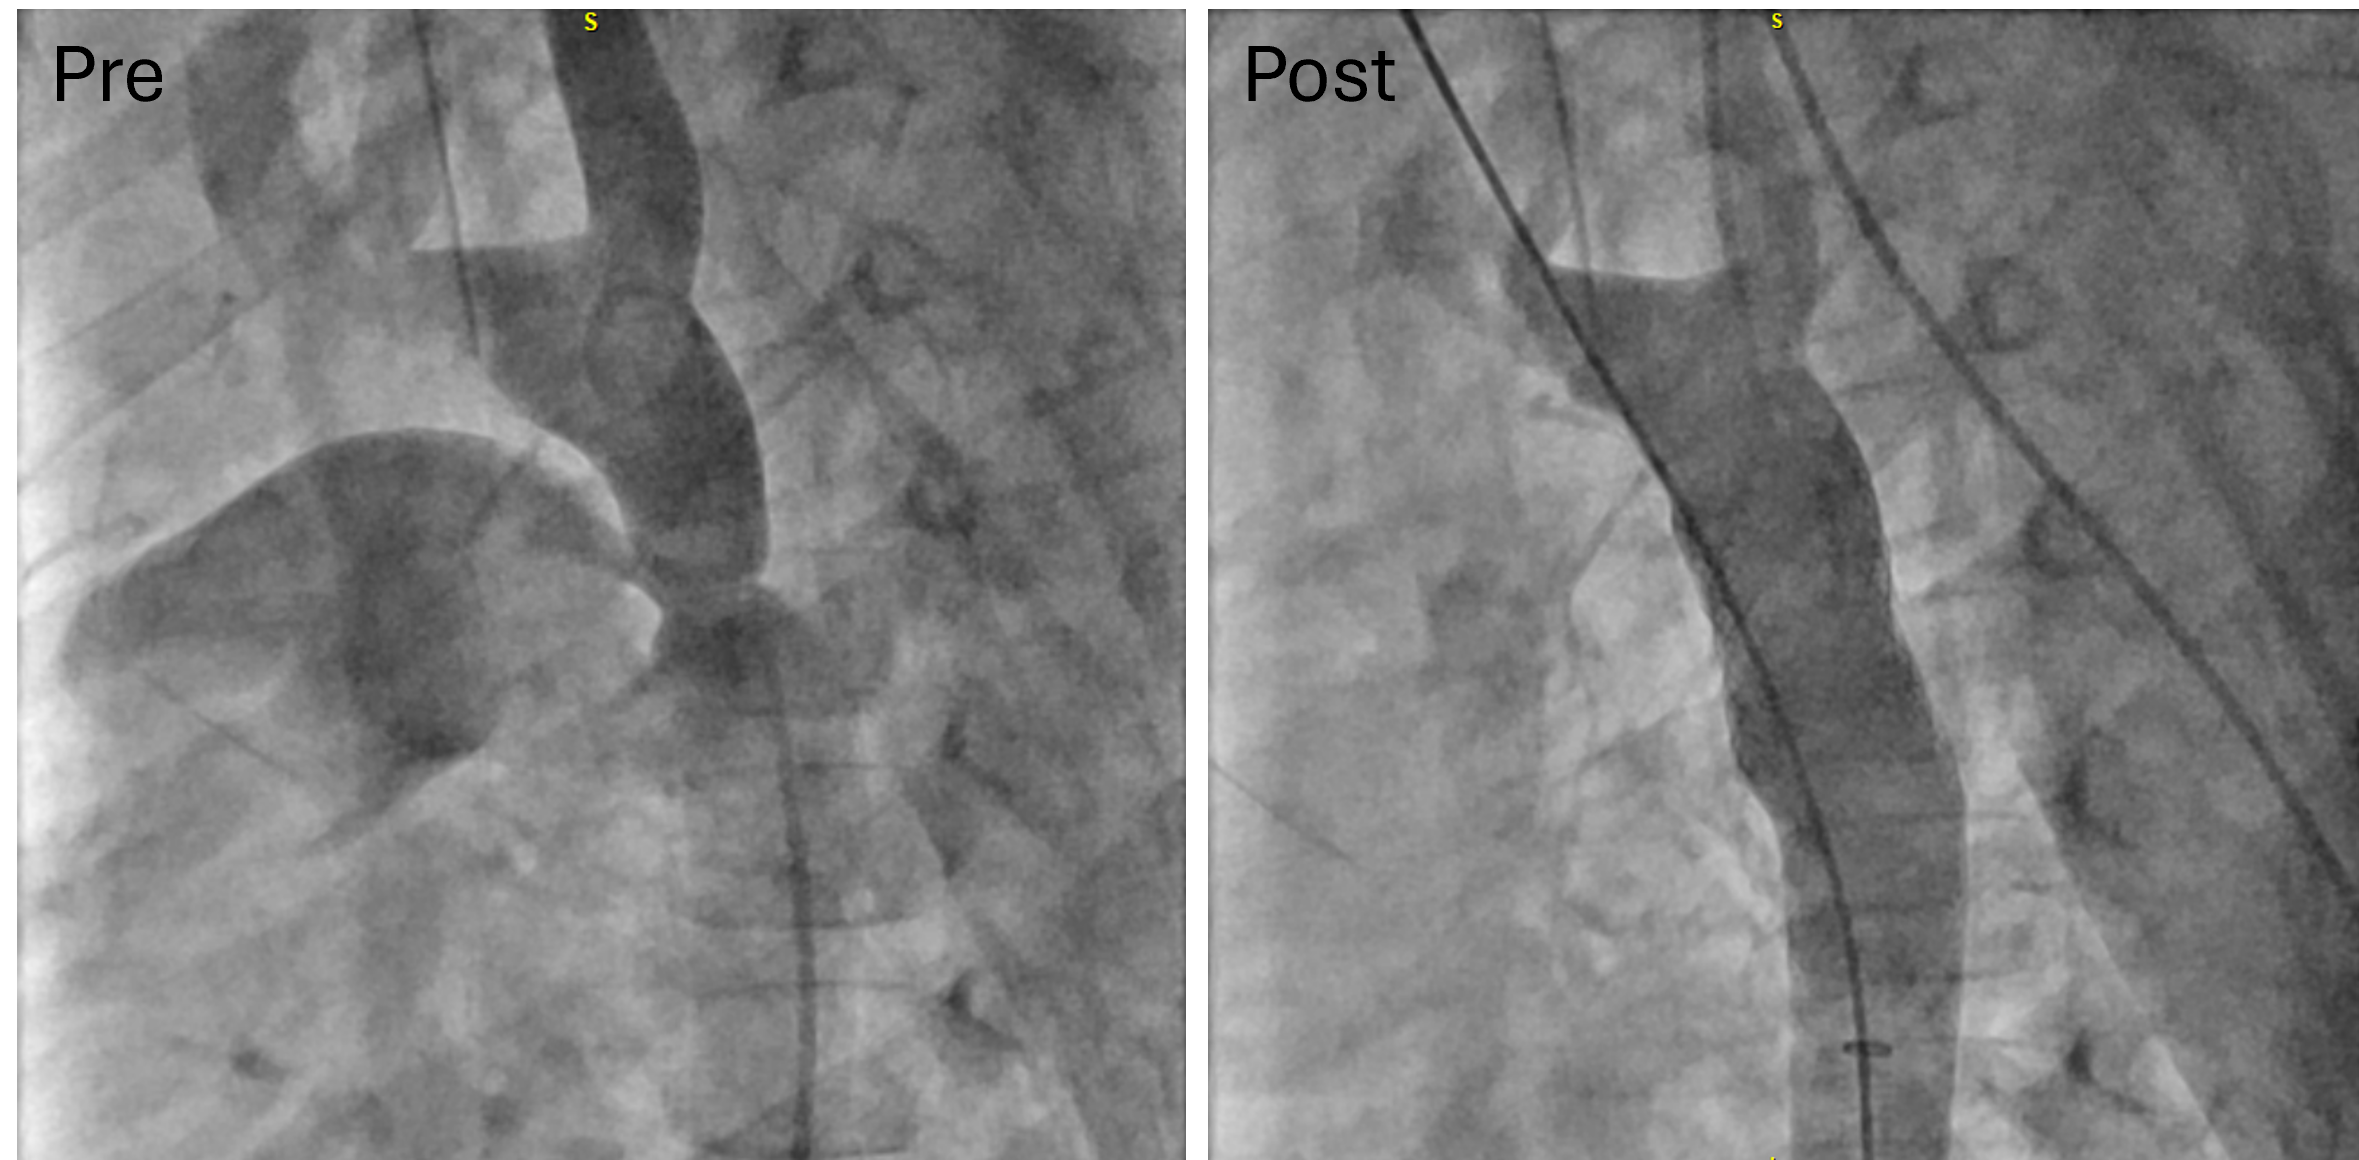

From a procedural standpoint, general anesthesia was utilized in 17 of the 23 procedures, while monitored anesthesia care was provided for the remaining 6 procedures. The patients typically underwent right heart hemodynamic catheterization, coupled with angiography for those with RVOTO, PAS, and SVS (Figures 1-3, pre). Additional retrograde left heart hemodynamic catheterization and angiography were performed for the patients with CoA (Figure 4, pre). The delivery sheath was as small as 7-French (Fr) in the femoral vein for the patients with RVOTO, PAS, and SVS, and 8-Fr in the femoral artery for patients with CoA, with ultrasound confirmation of a femoral arterial diameter greater than 3 mm prior to access in smaller patients. Stent size and pre-mount balloon diameter were chosen based on targeted pre-/post-stenotic vessel diameter, in addition to minimum waist diameter to allow secure delivery. Length was determined for adequate coverage of the targeted lesion. Rapid right ventricular pacing was performed only for CoA stent implantations. Selective post-implantation dilation with a non-compliant balloon was performed as needed to achieve the targeted diameter. Post-implant ultra-high-pressure dilation (≥ 20 atm) was performed on 8 stent grafts for full expansion (Table 2). Post-implantation angiography (Figure 1-4, post) and hemodynamic measurements were analyzed for all cases (Table 2).

The stent graft is also designed with independent tines rather than a continuous frame, conferring superior flexibility and enabling segmental flaring. This feature is advantageous for trackability over a wire in small pediatric patients, particularly those with branch PA stenosis (Figure 2). In addition, treatment of patients post-LeCompte maneuver may risk the creation of aorto-pulmonary fistula creation, so a covered platform is ideal.6 The flexible frame may allow for a more rounded implant shape contouring to the aorta. The non-contiguous frame also allows for segmental flaring; this creates a funnel into the stent that allows for ease of wire passage and entry upon re-intervention. The additional flexibility of this design leads to improved navigation through the calcified or acutely angulated regions of the RVOT, thereby delaying the necessity for surgical intervention in pediatric cases (Figure 1).

The low profile of the stent graft is also advantageous for small pediatric patients because it minimizes the risk of access site complications. We have previously detailed the technique for transcatheter palliation for CoA in young children (Figure 4).4,9 The 8L configuration, pre-mounted on an 8-mm balloon, is designed to go through a 7-Fr sheath. Recently, a new set of lower profile stent grafts has become available, with some designed to go through a 6-Fr sheath.